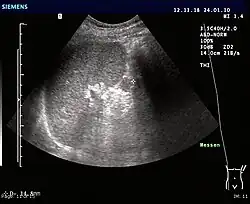

Ultrasonography of an accessory spleen.

If splenectomy is performed for conditions in which blood cells are sequestered in the spleen, failure to remove accessory spleens may result in the failure of the condition to resolve.[1] During medical imaging, accessory spleens may be confused for enlarged lymph nodes or neoplastic growth in the tail of the pancreas,[5] gastrointestinal tract, adrenal glands or gonads.[2]